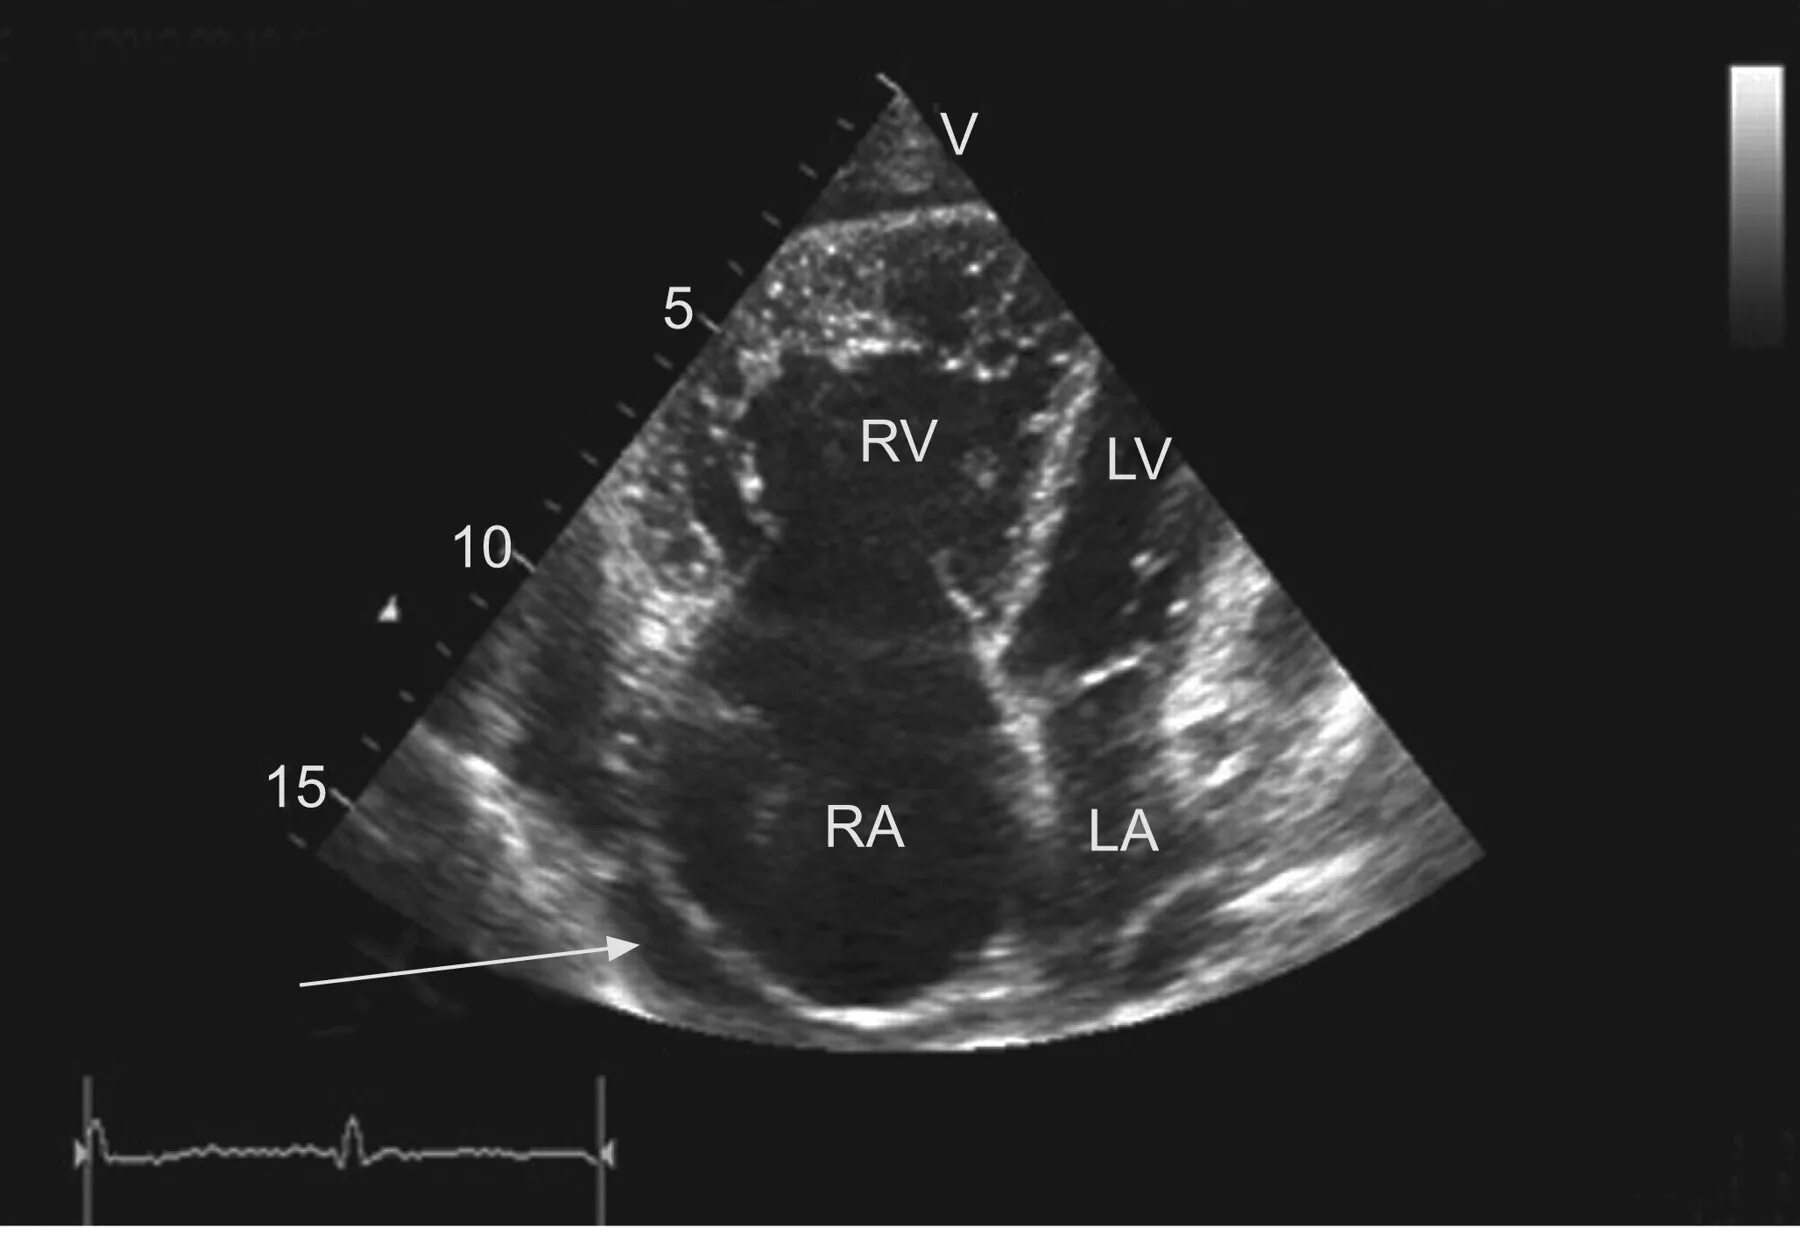

Эхокг сдла